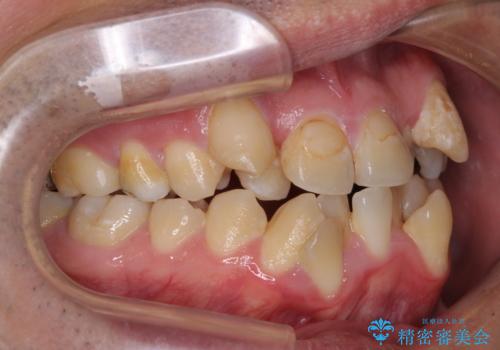

- 上下の八重歯やデコボコを気にして来院された患者様です。

上下ともに八重歯が顕著であったので、上下左右第一小臼歯4本を抜歯し、ワイヤー装置にて矯正治療を行うこととしました。

デコボコが強いことが原因で歯間部に汚れが溜まりやすい状態でしたが、矯正前にできる限り汚れが少なくなるようにブラッシングなどの指導を行い、口腔状態が改善された後にワイヤー装置を装着することとしました。